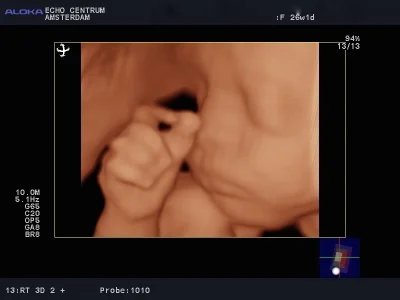

Vandaag was ik samen met mijn vrouw, moeder en neefje bij Dr. Papa. De naam alleen al maakt je vrolijk, dan zie ik mijn kleine mannetje weer op het scherm (oeps heb ik verraden wat het word). Dr. Papa legt alles zo haarfijn uit en het aller mooiste en belangrijkste is dat het kindje alles heeft en alles doet. In 3d zie ik zijn gezichtje en geloof het of niet, ik zie mijn kleine even lachen, mama zegt hij lijkt op jou, de glimlach die ik toen kreeg is er de hele dag gebleven, en nu ik dit schrijf verschijnt hij weer.

Wauw! Wat een bijzonder moment, het zien van ons eerste kindje in 3D! De neus van de een en de kleine krulletjes van de ander die al te zien waren. Te gek!

Vlinders in mn buik Wat een magisch moment toen we voor het eerst het gezichtje van ons kleine wondertje zagen, ze lachte en deed haar oogjes open, alsof ze naar ons gluurde. Dit is echt geweldig, nog helemaal aan het nagenieten. Ik kan iedere a.s. ouder Dr. papa aanbevelen.Hij geeft zeer heldere uitleg en heeft veel geduld en liefdevolle aandacht.

Vandaag onze nu al fantastische dochter gezien in 3 & 4D. Een magisch moment, want nu hebben we écht duidelijk beeld bij haar lieve, mooie snuitje en dat beweeglijke lijfje. Dat wat ik voelde is nu samengekomen met dat wat we van haar gezien hebben. Een waanzinnige ervaring! Heel veel dank dr. Papa, ook voor de heldere, begeleidende uitleg!